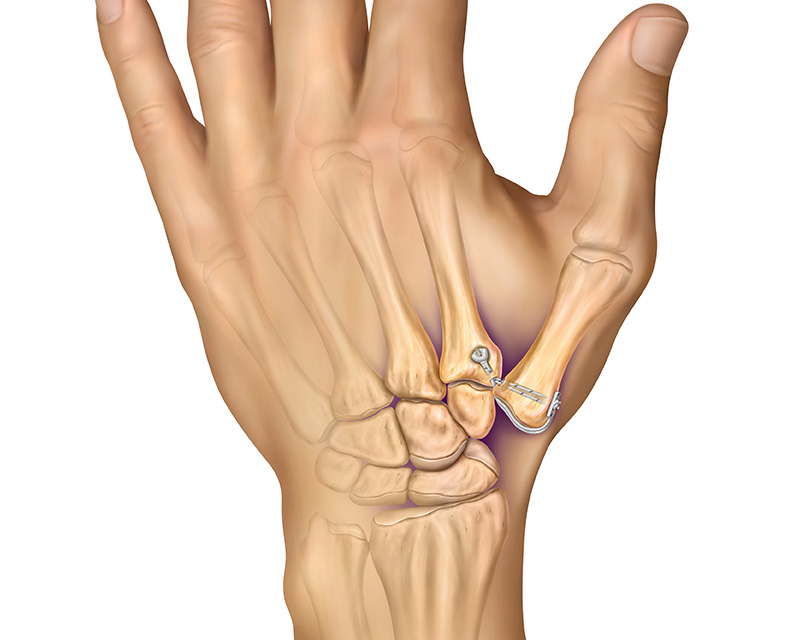

Anika’s Anatomic Thumb Ligament Arthroplasty System (ATLAS) is an anatomic thumb carpal-metacarpal (CMC) reconstruction device for use as adjunct fixation of the 1st and 2nd metacarpals in CMC arthroplasty.

The ATLAS technique corrects thumb CMC instability and provides rapid return to function by placing stable suture-based anchor fixation at the anatomic insertion sites of the thumb basal ligament.

- Suspensory CMC arthroplasty construct does not require a tendon graft harvest

- Anatomic repair maximizes recovery of normal thumb range of motion and rapid return to activities

- Single incision approach lessens wound healing issues and eliminates risk of disrupting the dorsoradial sensory nerve

- Small insertion footprint and sub-cortical fixation for a strong, stable, bone sparing technique with 54 lbf anchor pull-out strength1